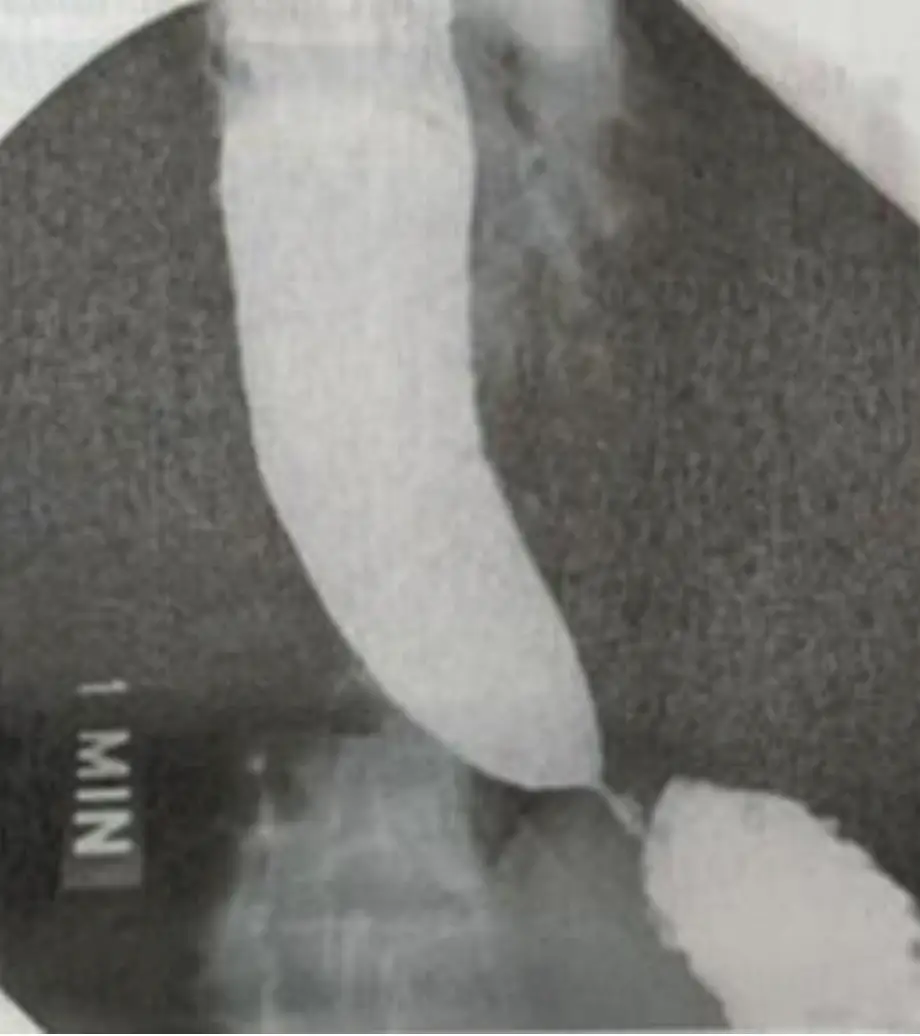

30歲男性患者有多年的嗆咳及吞嚥困難,接受食道攝影及檢壓術(manometry),結果如圖1、圖2,下列敘 述何者錯誤?(1)此病可以預防 (2)起因為下食道括約肌壓力太低 (3)可以用nitrate或calcium channel blocker治療,但效果有限 (4)可以用內視鏡擴張術(pneumatic dilation)治療,但不同中心有效結果報告 從30~90% (5)per oral esophageal myotomy (POES)效果不錯,且較傳統外科手術恢復快 圖片描述 圖片描述

本題核心在於識別原發性食道achalasia的典型放射學與高解析度食道動力圖(HRM)表現,並釐清其病理機轉(LES高壓及肌間神經叢退化)、是否可預防,以及現行各種治療方式(藥物、氣囊擴張、POEM)的適應症與療效。

• 第一張影像(食道鋇劑攝影)顯示全長食道均勻擴張,最下段呈現典型「鳥嘴」狀(bird’s beak)狹窄,食物無法順利通過,下食道括約肌處呈現明顯錐形收縮。此為achalasia最經典的鋇劑攝影表現,反映食道體部無波動推進及LES持續收縮。